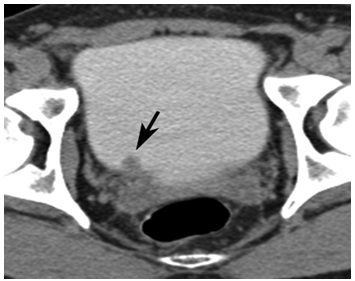

CTKUB showed a filling defect in the right lateral wall of bladder near vesicoureteric junction [Table/Fig-1]. Cystoscopy showed a mass lesion which measured 1.5x1x0.5 cm, over right vesicoureteric junction .Transurethral resection of the lesion was carried out and the sample was subjected to a histopathological examination. Grossly, the specimen consisted of grey white soft tissue fragments which measured 1.5x1x0.5 cm. Microscopy showed an ulcerated transitional epithelium with stromal oedema and congested blood vessels [Table/Fig-2]. There was diffuse infiltration of mucosa by eosinophils and few lymphocytes, with areas of haemorrhage and inflammatory necrosis [Table/Fig-3 and 4]. There was no evidence of malignancy or parasites in the sections which were studied.The patient was treated with corticosteroids, antimicrobial agents and antihistaminics and his post–operative period was uneventful. Until recent follow up, the patient was asymptomatic and there was no recurrence.

CTurogramsobtained during excretory phase show a 12-mm mass (arrow) near the right ureterovesical junction